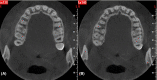

This report illustrates a rare case of a geminated maxillary right second molar tooth using CBCT in a 23-year-old man with severe pain. Nonsurgical endodontic treatment was performed, which gave rise to an asymptomatic tooth at the 12-month follow-up.